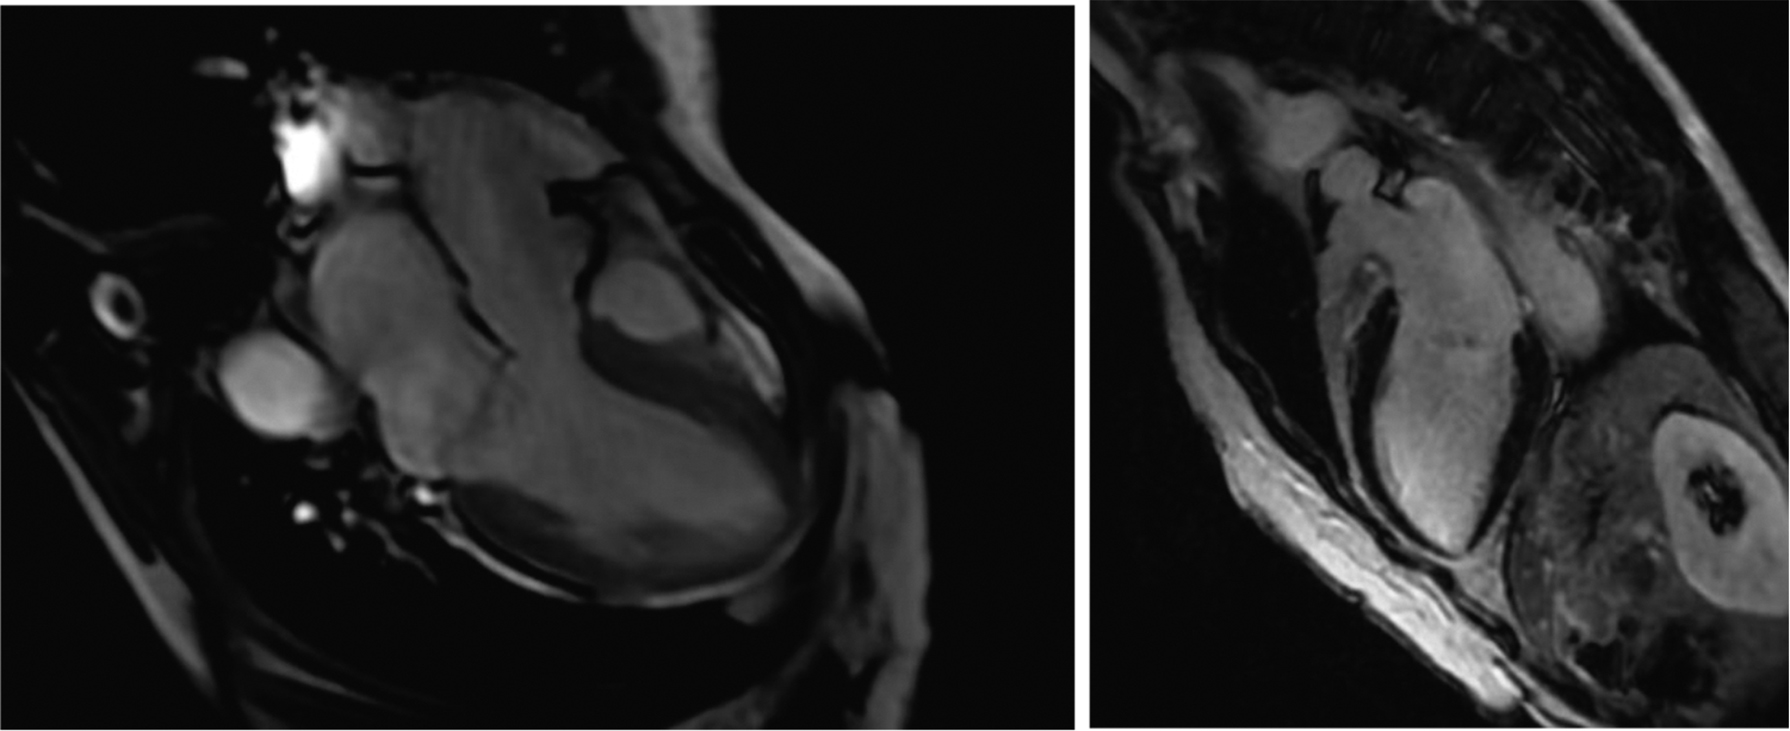

Для исключения перенесенного миокардита и выявления морфологического субстрата ЖНР пациентке была выполнена магнитно-резонансная томография (МРТ) миокарда с контрастом (гадолиний). МРТ сердца была проведена на томографе с индукцией магнитного поля 3 Т по стандартному протоколу с прицельной оценкой митрального клапана (рис. 5).

Рис. 5. Магнитно-резонансная томография миокарда. Фаза отсроченного накопления контрастного препарата

Сократительная функция по данным МРТ (в скобках указаны нормальные значения для возраста и пола): фракция выброса ЛЖ — 61 % (59–77 %), ударный объем — 84 мл (57–113 мл). Конечно-диастолический объем — 138 мл (86–166 мл). Конечно-диастолический объем инд. — 85 мл/м2 (56-90 мл/м2). Конечно-систолический объем — 54 мл (22–59 мл). Конечно-систолический объем инд. — 33 мл/м2 (14–33 мл/м2). Масса миокарда — 139 г (72–144 г), масса инд. — 87 г (48–78 г). При анализе изображений, полученных в режиме Cine, отмечался пролапс задней створки МК, признаков митральной аннулярной дизъюнкции не выявлено. На сериях отсроченного накопления контрастного препарата в объеме 20 мл признаки накопления в миокарде не определялись — данных о наличии воспалительных и фиброзных изменений не получено.